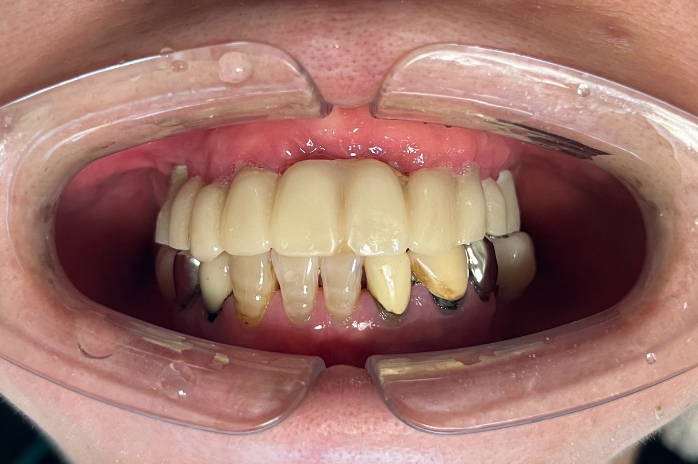

60代女性 AGC(全顎インプラント)

- AGC(全顎インプラント)治療

- 入れ歯を卒業したいと、全顎的なインプラント治療を決意されました。

- 特殊な「AGC構造」で作られるインプラントブリッジは、ネジも接着剤も使わず高精度の嵌合で固定されます。この患者様は6本で連結されており、簡単には外れませんが、専用器具で着脱可能です。丸洗いできるため衛生的で、将来的に介護が必要な場合も対応しやすいなどの特徴があります。